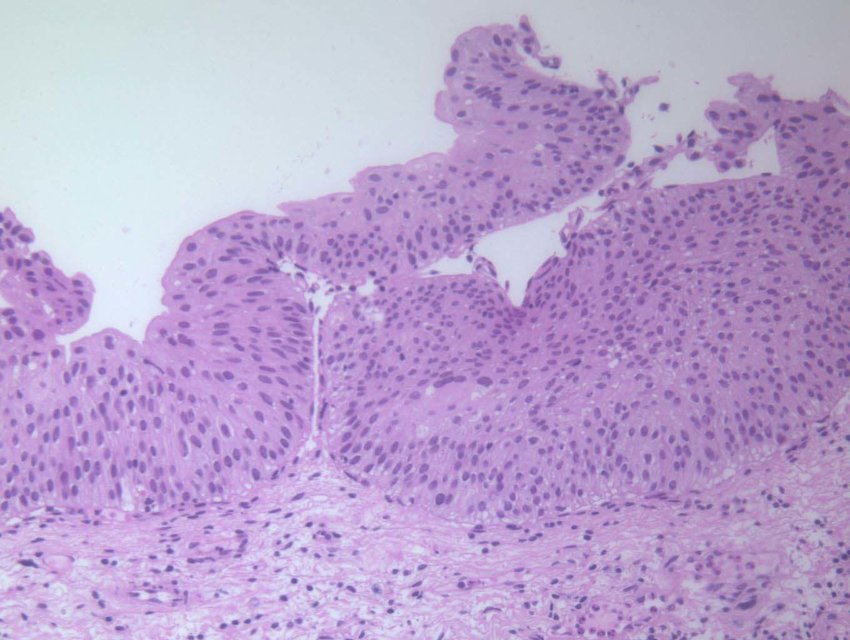

Normal urothelium

5-7 cells thick with umbrella cells at the top

Unlike squamous epithelia, these cells do not significantly mature as they reach the surface. Nuclei are 2-3x the size of lymphocytes and oriented perpendicularly to the epithelium.